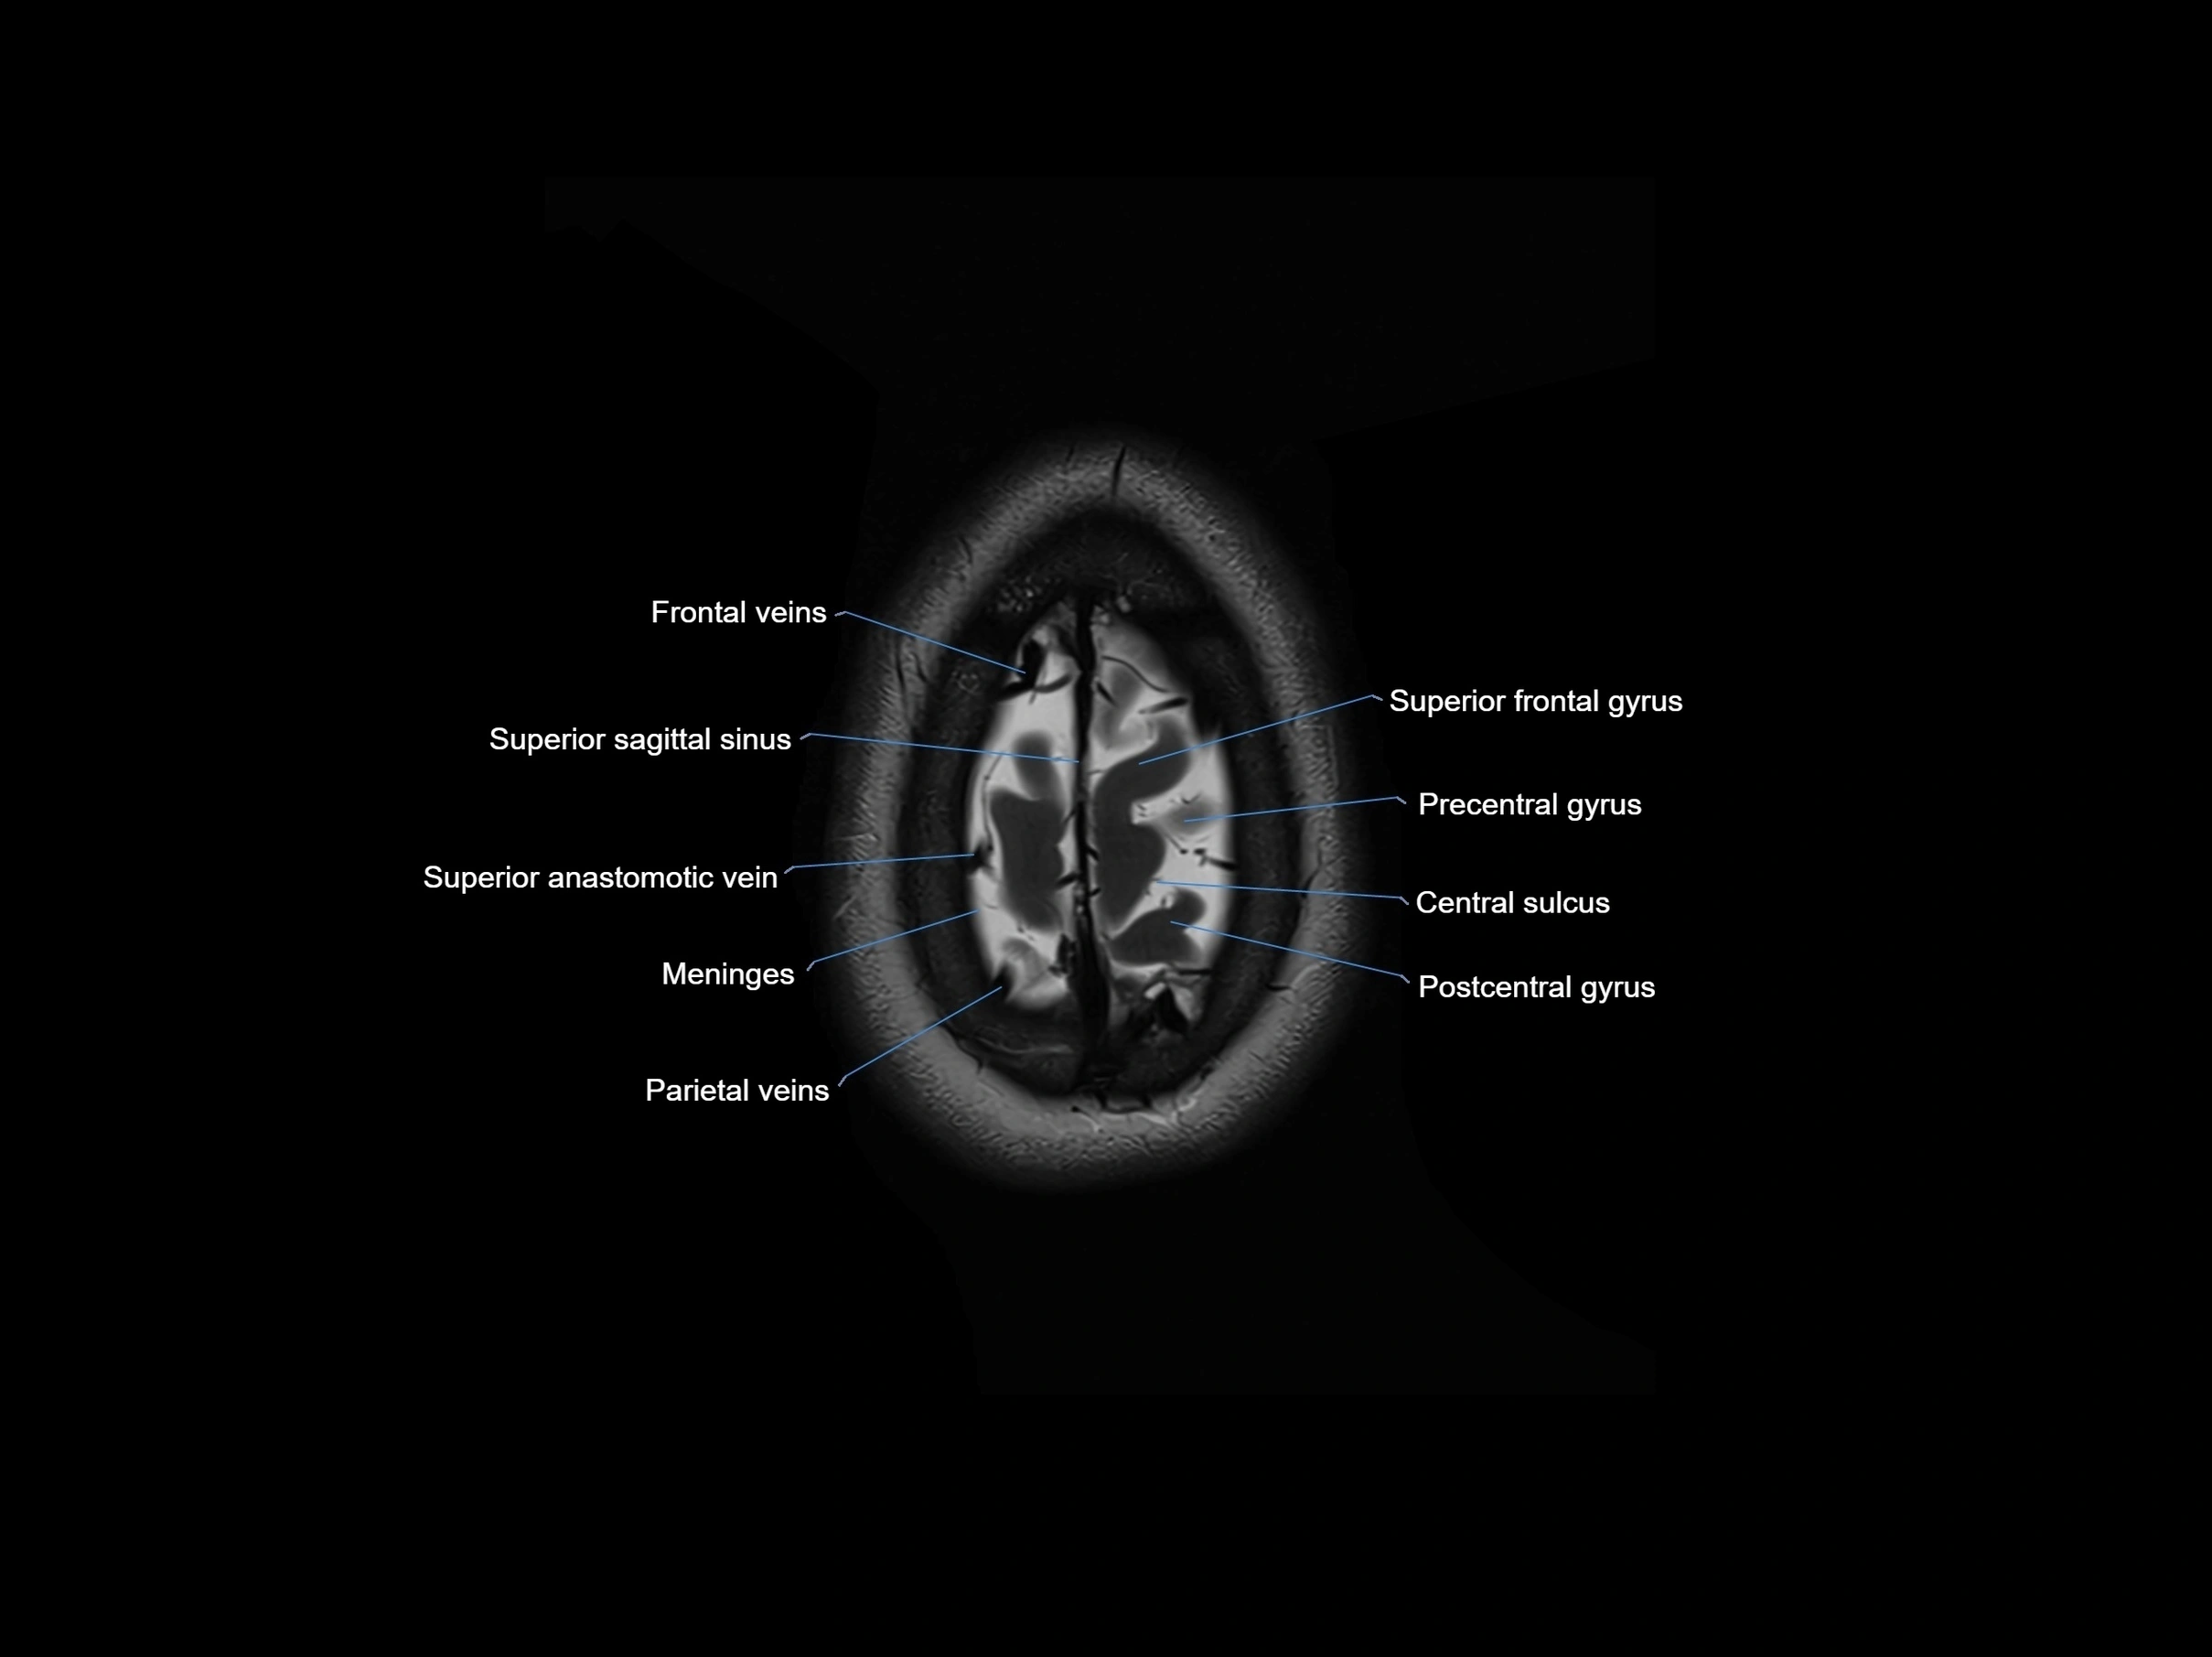

- Frontal veins

- Meninges

- Parietal veins

- Postcentral gyrus

- Postcentral sulcus

- Precentral gyrus

- Precentral sulcus

- Superior anastomotic vein

- Superior frontal gyrus

- Superior sagittal sinus

- Central sulcus